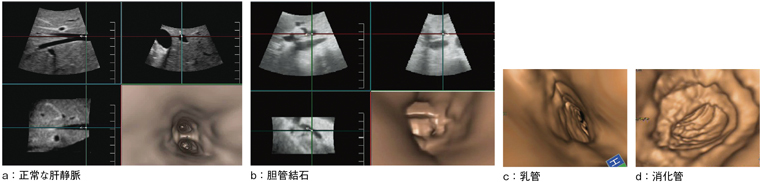

High Density Renderingとは,高速な3D/4DのVolume Rateを実現する新エンジンである。3D/4D画像が高速かつ高画質に得られる(図9)。4Dプローブにより構築した3D画像の管腔を内側から観察する“Fly Thru”は,膵管,胆管,尿管,血管,乳管,消化管など幅広い領域で期待が持たれる新機能である(図10)。

図10 Fly Thru